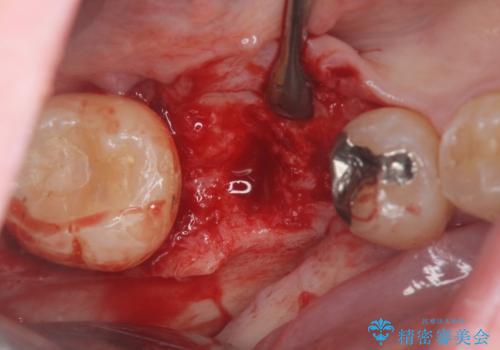

根だけ残った歯は、破折があり急性の炎症が認められ抜歯が必要な状態です。

抜歯後は、前後の歯を削らずにしっかりと咬合力を回復できるインプラント治療を選択されました。

虫歯の放置により吸収してしまった骨も造成を行うことでインプラント周囲環境をしっかりと整えています。